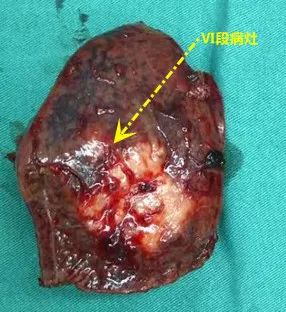

患者于近期完成手术治疗,我们在腹腔镜结直肠癌根治术及腹腔镜肝叶切除的经验基础上,实施了腹腔镜下联合脏器切除术,也是我院首例直肠癌肝转移患者采用腹腔镜下联合脏器切除术。为减少切肝的出血量,在麻醉手术部的通力配合下,术中尽量控制中心静脉的压力,手术得以顺利完成。

术后病理检查